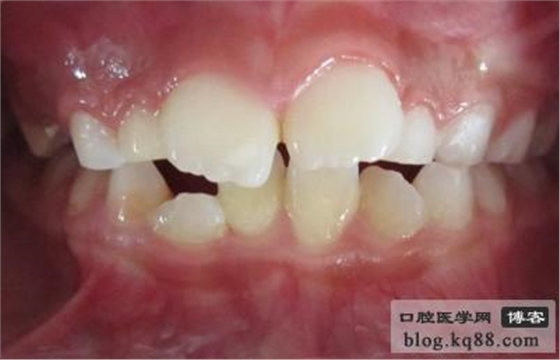

埋伏牙:各種原因?qū)е虏荒苷C瘸龅难馈?p style="text-indent: 2em; text-align: left;">1 埋伏牙形成的原因:牙齒萌出方向異?;蛎瘸鲩g隙不足導(dǎo)致牙齒萌出受阻,或牙齒萌出位置異常如恒牙胚位置過高,乳牙滯留或乳牙早失,恒牙胚發(fā)育期間外傷等原因都會導(dǎo)致牙齒無法正常萌出。

2 埋伏牙何時開始治療:牙根形成1/2以上時就應(yīng)開始治療,患兒家長在發(fā)現(xiàn)對側(cè)同名牙(對側(cè)相同位置的牙)已萌出一年而患側(cè)恒牙還未萌出時就應(yīng)到醫(yī)院就診,看是先天性恒牙缺失還是各種原因?qū)е碌穆穹馈?p style="text-align:center">

2.與替換期或與同名牙相比遲萌明顯。

3.需助萌的牙已達牙槽嵴頂部,切端在齦黏膜下,可被捫及,但因局部軟組織致密,萌出困難者。